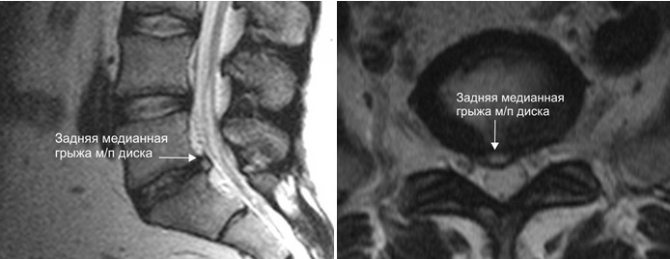

Образование медианной грыжи межпозвонкового диска возникает при его деформации. Внутреннее полужидкое содержимое диска (пульпозное ядро) прорывается наружу сквозь плотную фиброзную оболочку и выпячивается в центр канала позвоночника.

Здесь речь пойдет о таких видах, как переднебоковые, заднебоковые и медианные. Поговорим немного подробнее о каждом из указанных видов. Переднебоковые грыжи находятся вне пределов передней полуокружности туловищ позвонков, при этом виде происходит прободение или отслаивание передней продольной связки. Такие грыжи могут стать причиной симпаталгического синдрома, если в процесс вовлечена паравертебральная симпатическая цепочка. Заднебоковые грыжи прободают соответственно заднюю часть фиброзного кольца проходя по средней линии (где бывают медианные грыжи), сбоку (так называемые латеральные грыжи) либо близ нее (парамедианные). Представляют такие грыжи наибольшую угрозу всему содержимому канала позвоночника. Срединные грыжи (медианные) нередко могут достигать ощутимо больших размеров и часто прободают заднюю связку (продольную), располагаясь эпидурально. Иногда они способны проникать даже сквозь твердую оболочку мозгового нерва далее в субарахноидальное пространство. Секвестр может свободно перемещаться как в нисходящем, так и в восходящем направлении. Парамедианные грыжи, как правило, возникают на уровне пары нижних дисков поясницы, где они вызывают компрессию корешков соответственно в l5 и s1 частях их отправления из дурального мешка.